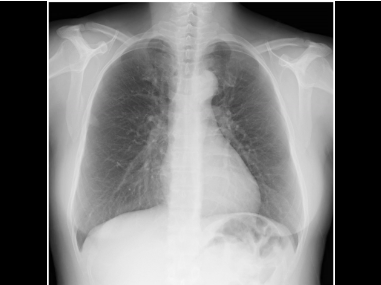

画像診断システムなどの医療向け製品・サービスを提供する「ヘルスケア事業」。コニカミノルタの強みである光学技術と画像処理技術を活かし、高品質なレントゲン装置や超音波診断装置、医療情報システムなどを提供しています。私たちが特に重視するのは「初期医療」への貢献。疾患の早期発見・早期治療を促進するために、病気を「みえる化」して診断をサポートしています。デジタルならではの最適化処理により診断しやすく、常に安定した高品位の当社医療機器は、医師不足が課題である地域医療や在宅医療の分野においても活躍しています。

ワイヤレスデジタルX線装置「AeroDR」

DRとは、診察時のレントゲン撮影に使用されるデジタルX線装置のこと。AeroDRはコニカミノルタの技術により、世界トップクラスの軽量設計を達成したワイヤレスタイプDRです。最も軽いモデルで、その重量はわずか1.7キログラム。女性や高齢の医療従事者も無理なく使用することが可能です。AeroDRで撮影された画像は、X線曝射後1秒台で撮影画像を高速表示することで、スムーズな診断を実現します。

当社の画像診断支援・業務支援AIは、医療現場の「見落としを防ぎたい」「業務負担を減らしたい」という声から生まれました。胸部X線画像を解析し、医師の読影を支援する画像診断支援AIや、撮影業務をサポートする業務支援AIによって、診断の確信度向上と業務効率化に貢献します。